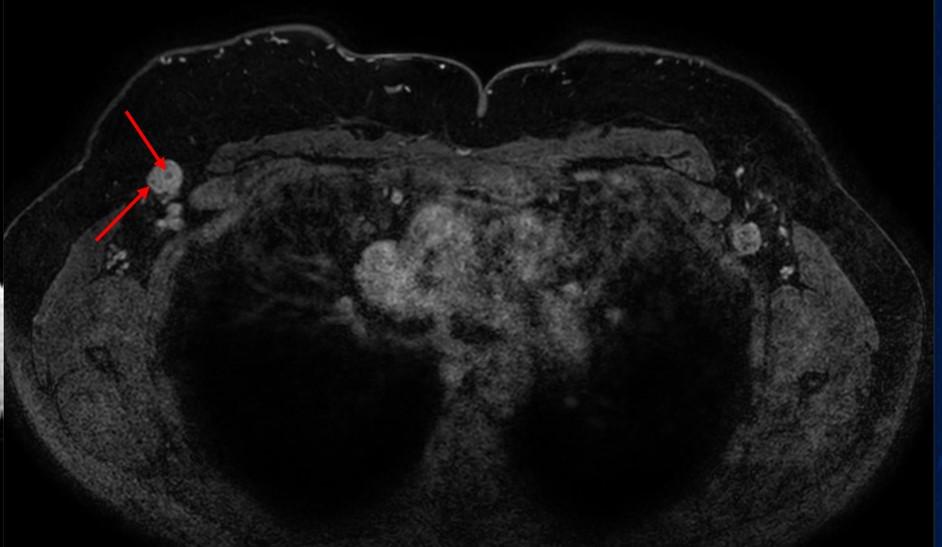

腋下MR影像显示双侧呈球形肿块,在T1WI上表现为低信号。在T1WI对比增强脂肪饱和影像中,可见腋下肿块呈异质性明显强化,伴有点状脂肪区域(图6、7)。

ccb86a91f6c48188bcd8ee7993601a4b.jpgf7ef49ccf18c7a0e3c51ddb77209d20f.jpg